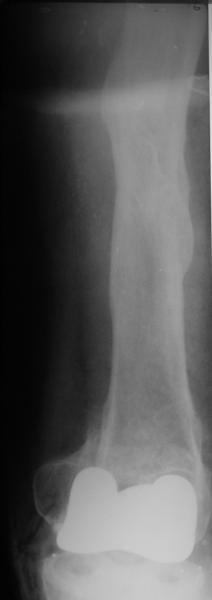

Добрый день! В нашу больничку поступил пациент после бытовой травмы - упал, подвернув ногу. На RG-граммах перелом дистального метаэпифиза бедренной кости. Пациент спутанно рассказывает, где и как он лечился раньше.10 лет назад - коррегирующая остеотомия по поводу деформирующего артроза коленного сустава, 3 года назад в 1 градской больнице г. Москвы выполнено эндопротезирование коленного сустава,площадка большеберцовой кости, со слов пациента, деформировалась около года назад (на фоне остеопороза). Сейчас получил травму в результате падения с высоты собственного роста.Что посоветуете?

Видимо, самое "модное" на сегодня - малоинвазивный остеосинтез пластиной с угловой стабильностью. Распространенный вариант и закрытый интромедуллярный остеосинтез ретроградно. Хотя у нас было бы сделано антеградно - лешево и сердито, действительно малоинвазивно, в сустав не надо влезать. Нет риска прорезания порозной кости с миграцией в сустав, что возможно при ретроградном - гвоздь вводится через вырез в бедреннм компоненте, туда же может и вывалиться. А антеградный - упрется в протез. Как раз вчера заходил больной через полтора года после такой операции. Снимки в приложении.